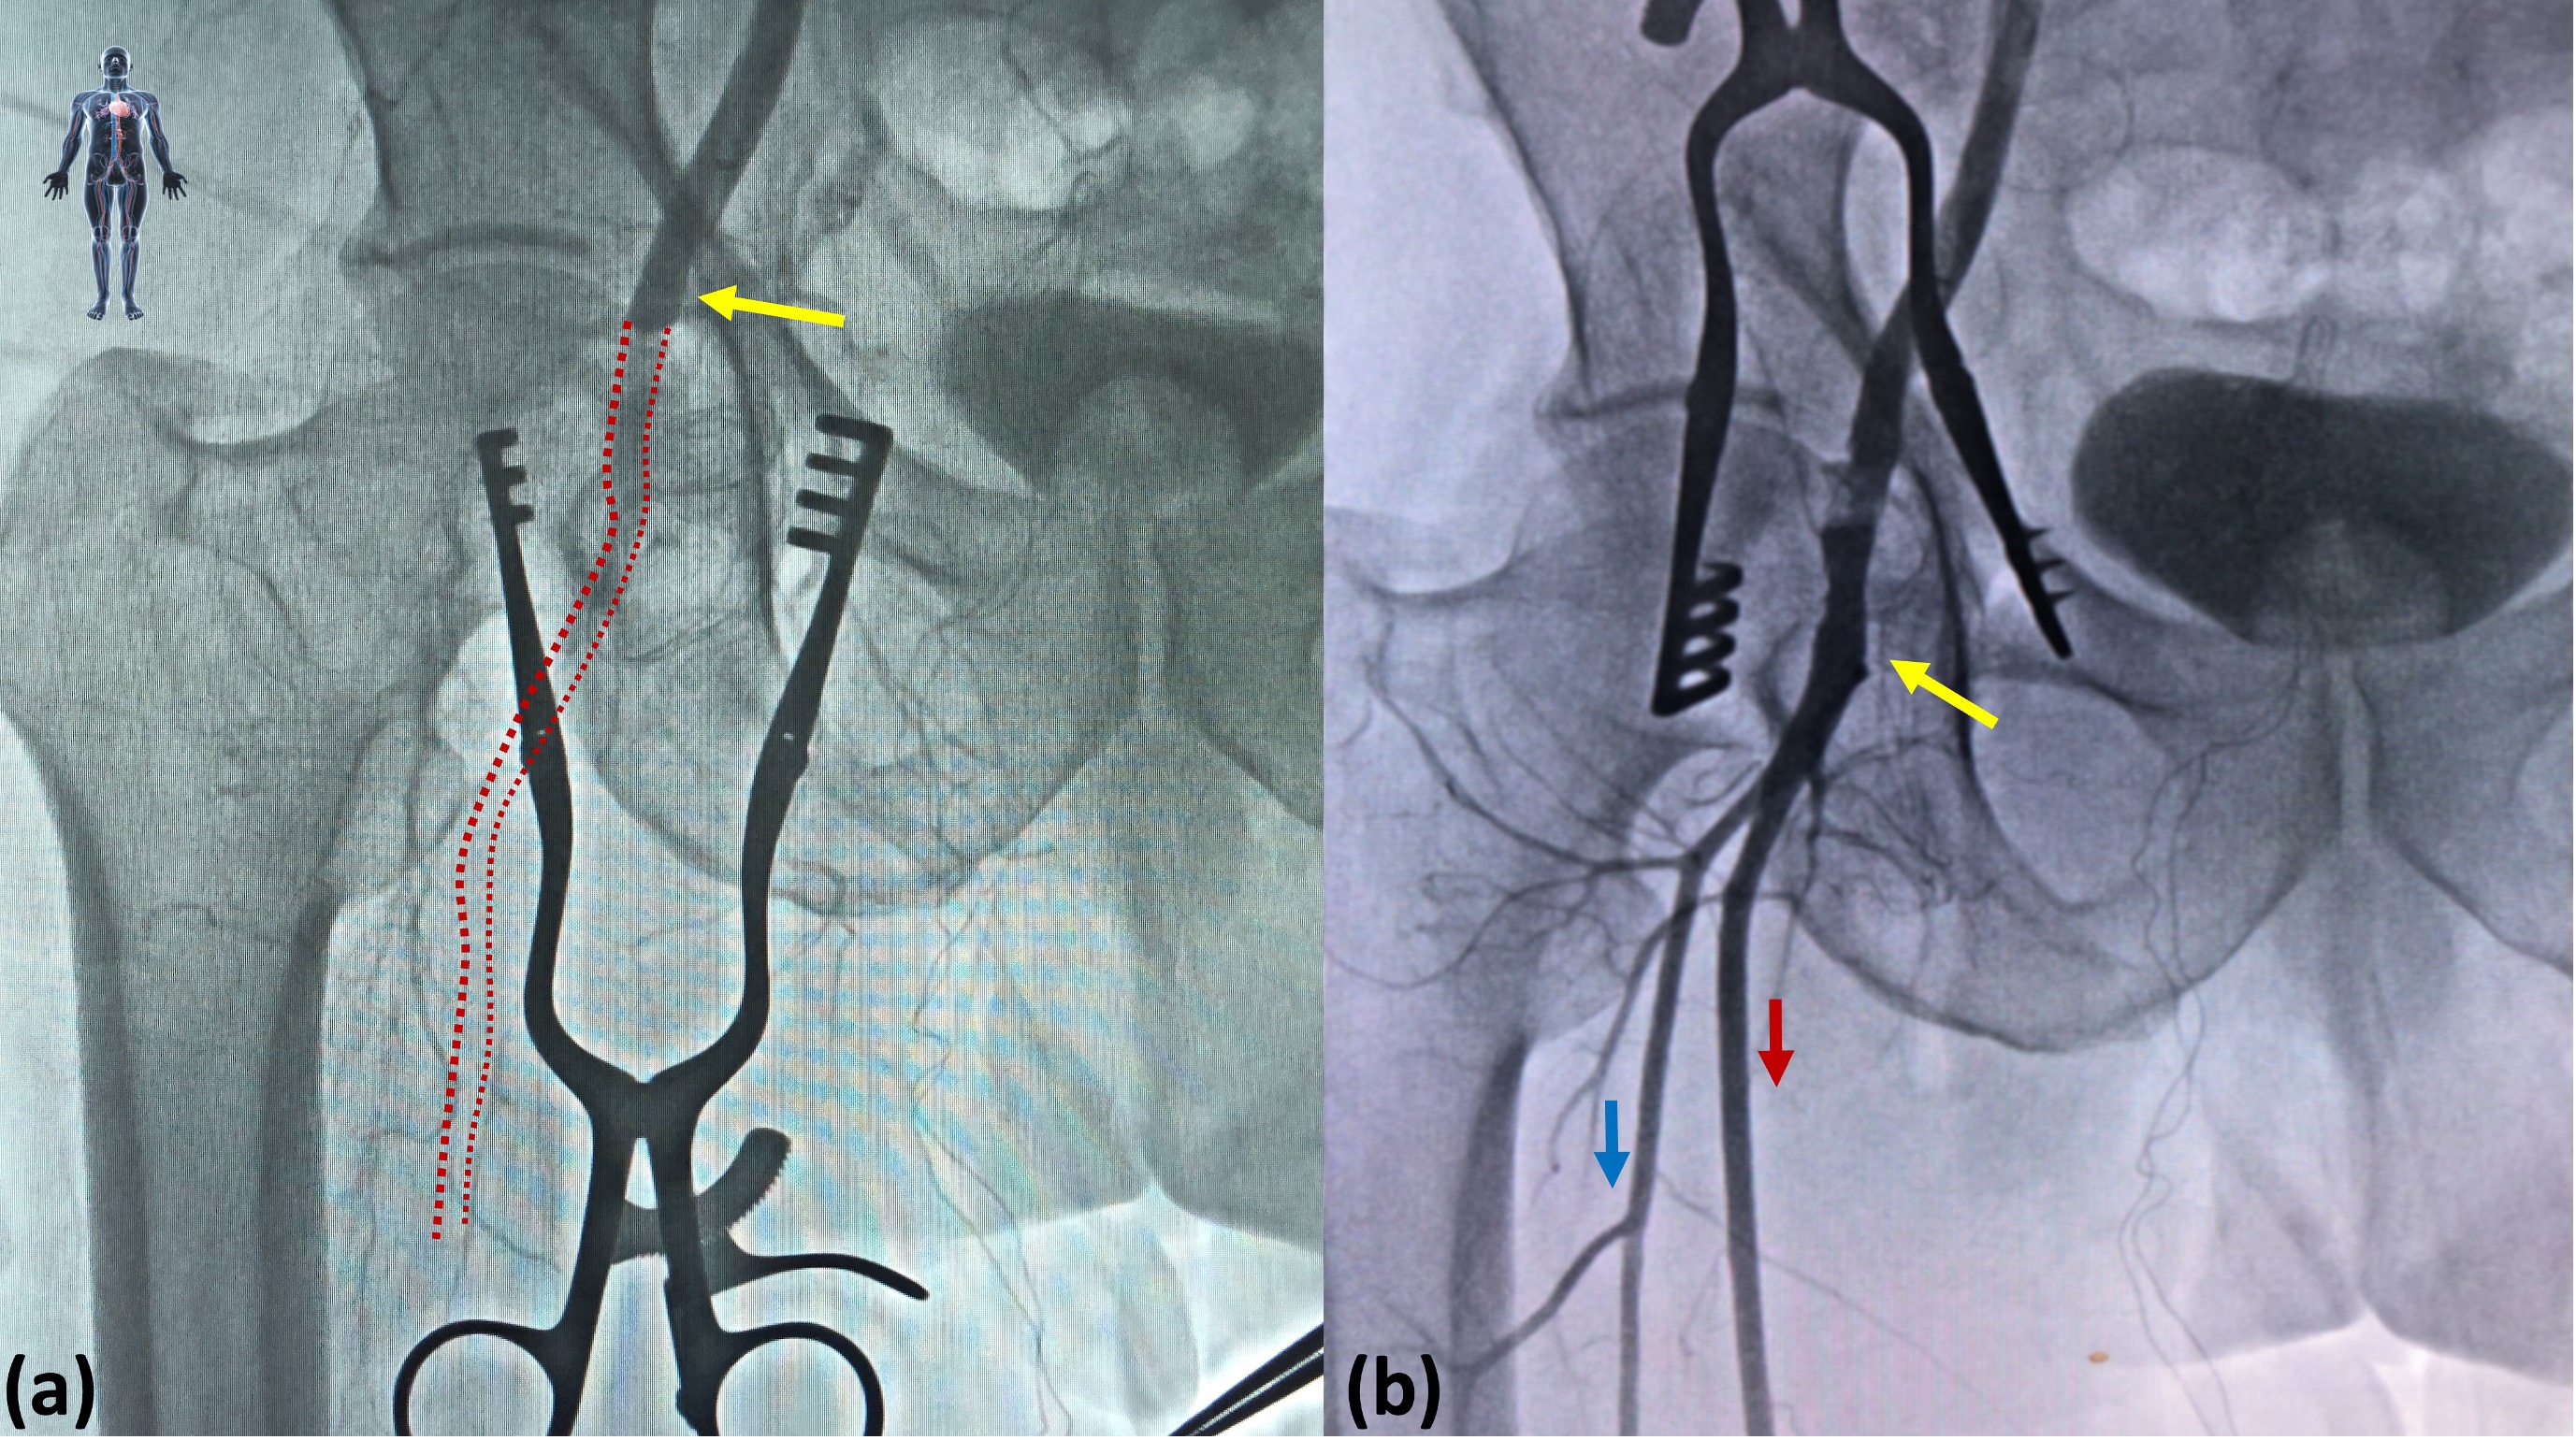

The number of SBVCDs that were used for LBA site closure were as follows: 1 SBVCD in 1 patient, 2 SBVCDs is 13 patients, and 3 SBVCDs in 11 patients. Minor complications at the access site, such as groin hematoma, were observed in 92% of patients; pseudoaneurysm of the access artery was seen in 16% of patients; and an arteriovenous fistula was observed in 8% of patients. Major complications of retroperitoneal hemorrhage and acute limb ischemia of the access site limb was observed in 88% and 92% of patients, respectively. All-cause 30-day mortality was observed in 5 patients (Table). The emergency surgical intervention offered to the patient included vein patch angioplasty (Figure 1), prosthetic patch angioplasty (Figure 2), interposition graft (Figure 3), and covered stent deployment (Figure 4).

Acute limb ischemia of the ipsilateral limb was the most common major vascular complication observed in the study (FIgure 6). All the limbs were revascularized in the study. Only in 1 case did the profunda femoris artery have to be jailed during covered stenting for SBVCD failure as the patient was hemodynamically unstable post transcatheter aortic valve implantation procedure and required immediate hemorrhage control. The 30-day all-cause mortality in our study was quite high, and the available literature on the subject labels it as a major event associated with SBVCD failure worldwide.4,7,9 The probable reason for this high mortality can be attributable to the high surgical stress exerted by the emergency intervention in a group of patients who have poor reserves and compromised cardiac functions.